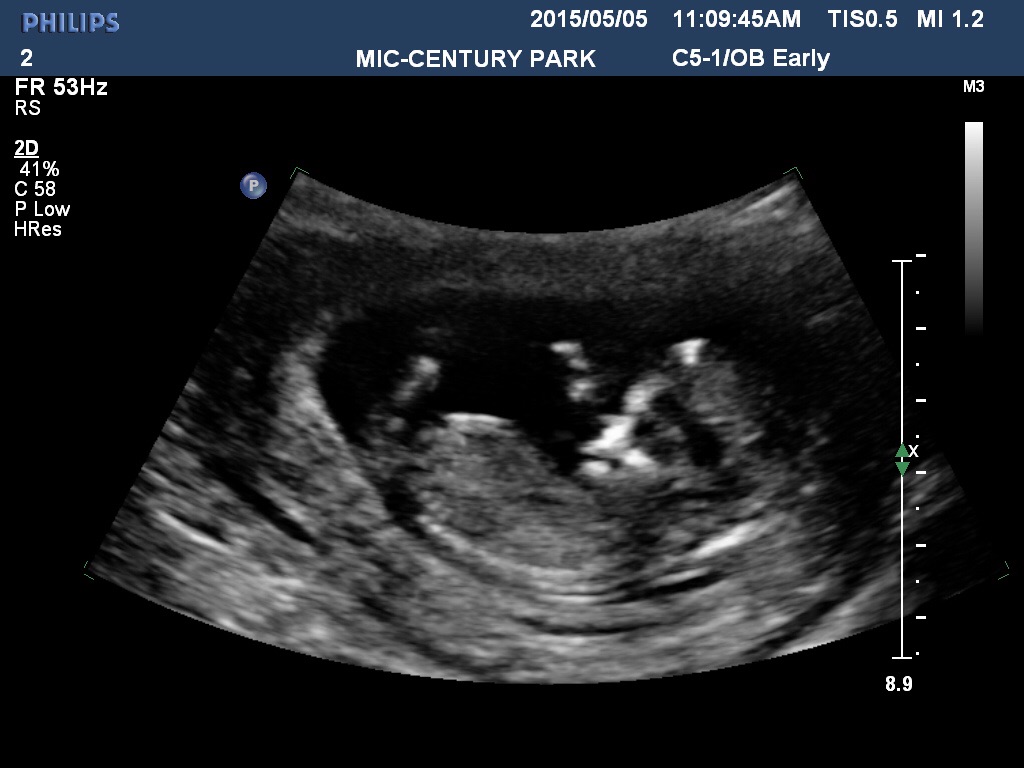

10 weeks 4 days yesterday.... Was waving and squirming all over... HR was 173.... So amazing... Get genetics test results and gender back in 7-10 business days!